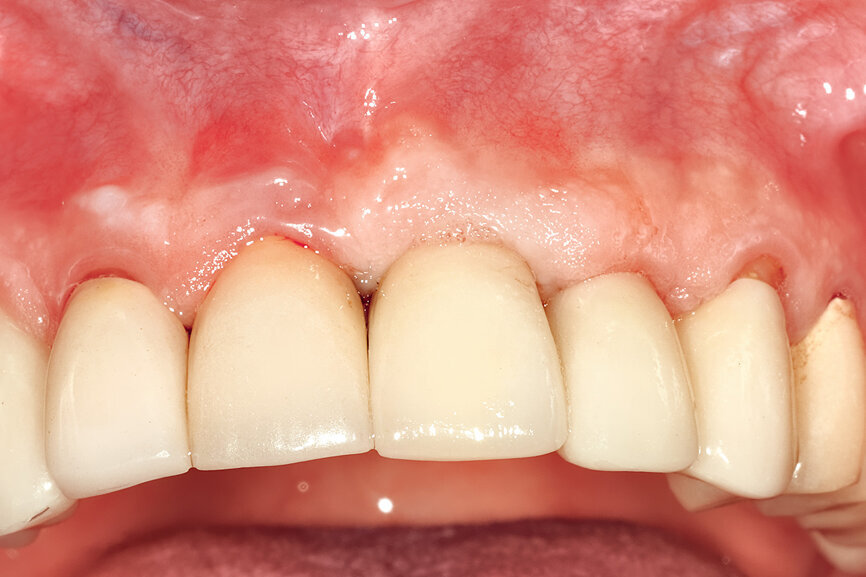

Fig. 26c: The abutment in place.

Fig. 26d: The soft-tissue contours were excellent; no sutures were required for the transitional restoration.

Fig. 29: The definitive restoration exhibited excellent retention of the soft-tissue profile.

Fig. 30a: The occlusal view revealed the volume maintained with

the soft-tissue cervical contours (a), and the lateral retracted view revealed an excellent soft-tissue emergence profile (b).

Fig. 30b: The occlusal view revealed the volume maintained with

The initial plan was for immediate extraction, immediate placement and immediate restoration. Therefore, it was essential to measure the implant’s stability with an objective technology, RFA, which provides an ISQ value utilising an implant-specific SmartPeg (Osstell; MEGA ISQ, MegaGen). The baseline ISQ value (76) confirmed sufficient initial stability to place an immediate restoration (Fig. 25). The prefabricated CAD/CAM abutment was then secured to the implant, and a postoperative periapical radiograph confirmed successful sub-crestal placement for this platform-switched design (Fig. 26a). The transitional acrylic restoration was then placed and examined for any occlusal interferences (Fig. 26b). It was important that the restoration be out of occlusion to avoid premature forces that could complicate integration. The soft-tissue contours were excellent, and no sutures were required, since no flap was raised (Figs. 26c & d). After a period of eight weeks, the implant stability was measured to be at 80 ISQ, confirming that the integration process had continued to progress successfully and that the implant was ready for the definitive restoration. An intra-oral scanner and scanning abutment were then utilised to capture the position of the implant and soft-tissue emergence profile. The post- operative CBCT scan revealed the intact crescent shape of the root membrane (Figs. 27 & 28). The definitive restoration was then delivered and exhibited excellent retention of the soft-tissue profile (Figs. 29 & 30).